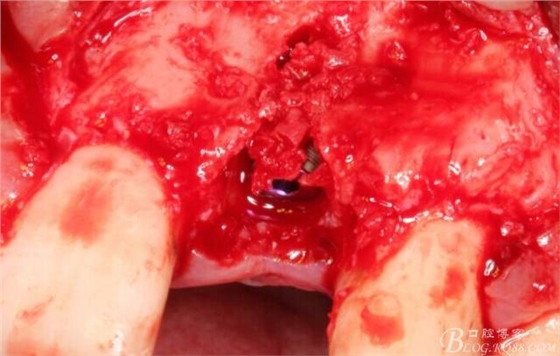

翻開(kāi)后驚喜的發(fā)現(xiàn),術(shù)區(qū)成骨非常好,去除部分骨才暴露那顆長(zhǎng)鈦釘。

取出影響種植入路的長(zhǎng)鈦釘。

擴(kuò)孔。

骨擠壓。

植入植體。